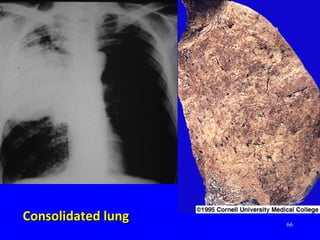

Consolidated lungConsolidated lung

58 Pneumococcal pneumoniaPneumococcal pneumonia Rupper lobe consolidationR upper lobe consolidation